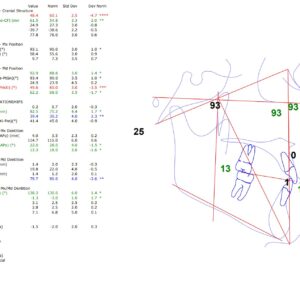

Análisis De Ricketts En Studio Digital Imaging

El análisis dental de Ricketts es un enfoque utilizado en ortodoncia y ortopedia dentofacial, diseñado para evaluar y planificar tratamientos de maloclusiones y problemas relacionados con la oclusión dental. A continuación, se presentan los puntos clave de este análisis: Principios Básicos Ricketts establece un sistema de medidas y relaciones entre los dientes, las arcadas y...